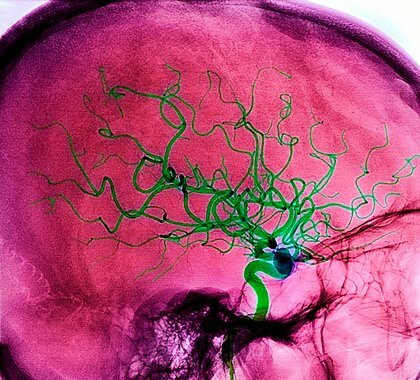

Современное лечение острого нарушения мозгового кровообращения  Острое нарушение мозгового кровообращения, или инсульт – заболевание, которое вызвано ишемией или геморрагией сосудов, питающих часть головного мозга, или кровоизлиянием в оболочках мозга. В классификации инсультов существует два вида заболевания: геморрагический инсульт и ишемический инсульт. Современное лечение острого нарушения мозгового кровообращения направлено на устранение причин инсульта, а также реабилитацию больных в процессе лечения.

Ишемический инсульт в своей основе имеет закупорку отрывающимися атеросклеротическими бляшками сосудов головного мозга, или тромбами от клапанов сердца, спазмами сосудов.

Геморрагический инсульт происходит в результате разрыва сосуда головного мозга при высоком давлении. При атеросклерозе стенка сосудов неравномерно истончена, и разрывается в месте наибольшего истончения. Кровь под давлением заполняет полость в тканях мозга. Иногда причиной геморрагического инсульта является разрыв аневризмы сосуда.